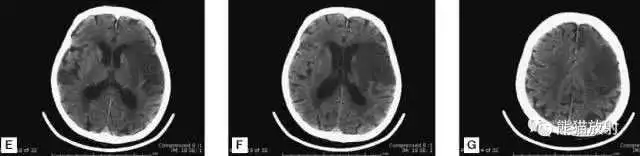

A:陈旧性脑梗死,右枕叶体积缩小;

B:左枕叶急性脑梗死,灰白质分界模糊,脑沟消失;

另一患者:

C、D:亚急性期脑梗死,低密度,无明显占位效应。